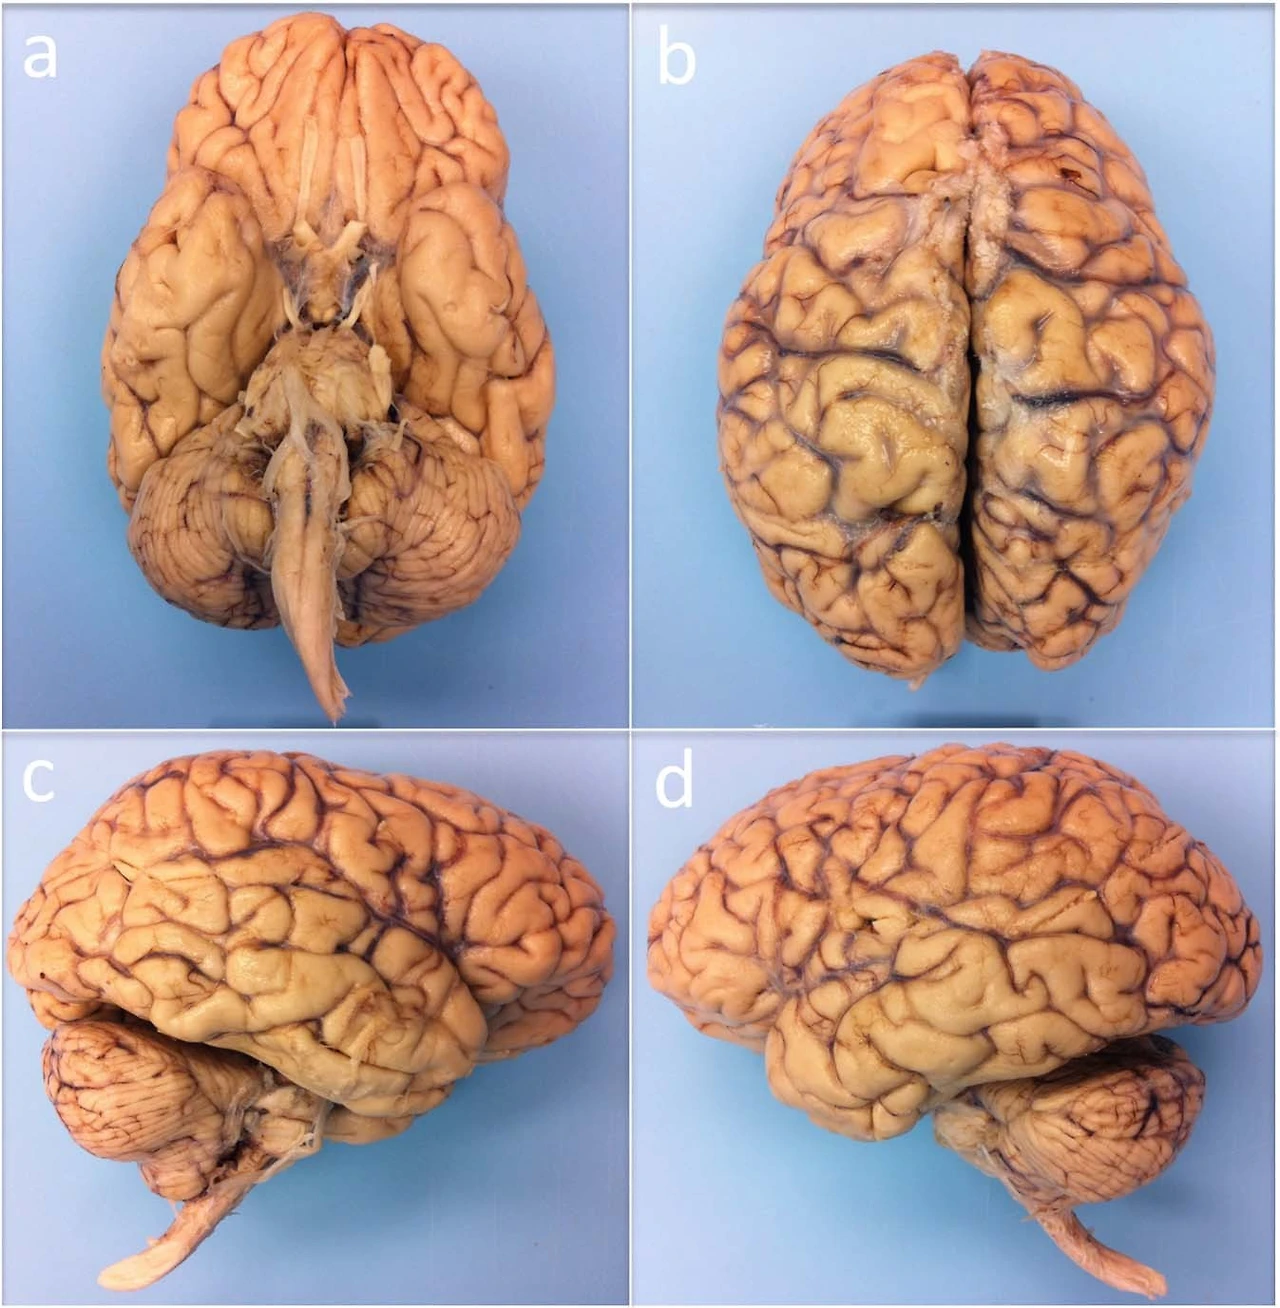

나의 전공은 뇌과학이다. (말할 필요도 없이) 뇌에 대한 여러 지식을 공부하는 것이 나의 일인데, 문득 첫 이 길을 걷게 된 계기를 생각해 보면, 아직도 우리가 완벽히 이해하지 못하는 뇌라고 하는 지구에서 가장 복잡한 생명 조직에 대해, 어떻게 이러한 유기적 토대가 정신을 만들어낼 수 있는지에 대하여 더 알아보고자 했던 마음이 그 시작점이었다(그림 1).

그림 1. 실제 인간의 뇌. 보통 이와 같은 실험용 조직은 핏기를 제거하고 화학 용액을 통해 방부처리를 하는데, 그런 처리를 하지 않은 뇌는 선홍빛을 띤다. Edlow, 2019.